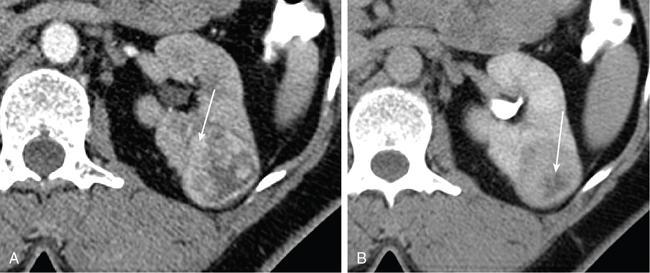

IMAGING OF RENAL MALIGNANCIES IN ADULTS Aparna Katdare, Palak Bhavesh Popat, Nilesh P. Sable, Ganesh Bakshi, Suyash Kulkarni Detection of renal masses has increased remarkably in recent times owing to wide-spread use of cross-sectional imaging. Imaging plays an important role in characterizing renal masses and is indispensable in treatment planning in renal malignancies. The most commonly encountered malignant renal masses in practice include renal cell carcinoma (RCC), urothelial carcinoma, lymphoma and metastases. Urothelial carcinoma and lymphoma have been covered in detail in separate chapters. RCC constitutes nearly 90% of all renal malignancies with a higher incidence in North America and Europe than India, Africa and China. With an increase in the number of cross-sectional studies performed, especially in Western population, the incidental diagnosis of RCC has increased in recent times, with such incidentally diagnosed lesions presenting at earlier stages with better prognosis and reduced rates of recurrence. The median age of presentation of RCC is 64 years according to the Surveillance, Epidemiology and End Results (SEER) program database and almost a decade earlier in Indian population, with a definite increasing risk of RCC with increasing age. Males are affected about 2–3.5 times more than females. In the Indian population, patients have been seen to present at a later stage as compared to the Western population. Amongst the various postulated risk factors, there is convincing evidence that smoking, hypertension, obesity and acquired renal cystic disease increase the risk of RCC. Alcohol intake and physical activity have been found to be associated with reduced risk of RCC. Trichloroethylene and cadmium exposure have been postulated as likely causes as well. Two to four per cent of RCCs are hereditary, with association of various genetic disorders such as Von Hippel Lindau (VHL) syndrome, hereditary papillary renal carcinoma, hereditary leiomyomatosis RCC, Birt-Hogg-Dube syndrome, chromosome 3 translocation and tuberous sclerosis (TCS1, TCS2). The WHO classification of 2016 (Table 11.25.1.1) stratifies tumours of the kidney into different subtypes based on cytoplasmic and architectural features, tumour location, background renal disease and molecular alterations. Clear cell renal cell carcinoma Multilocular cystic renal neoplasm of low malignant potential Papillary renal cell carcinoma Hereditary leiomyomatosis and renal cell carcinoma-associated renal cell carcinoma Chromophobe renal cell carcinoma Collecting duct carcinoma Renal medullary carcinoma MiT family translocation renal cell carcinomas Succinate dehydrogenase-deficient renal carcinoma Mucinous tubular and spindle cell carcinoma Tubulocystic renal cell carcinoma Acquired cystic disease-associated renal cell carcinoma Clear cell papillary renal cell carcinoma Renal cell carcinoma, unclassified Papillary adenoma Oncocytoma 8310/3 8316/1a 8260/3 8311/3* 8317/3 8319/3 8510/3a 8311/3a 8311/3 8480/3a 8316/3a 8316/3 8323/1 8312/3 8260/0 8290/0 Metanephric adenoma Metanephric adenofibroma Metanephric stromal tumour 8325/0 9013/0 8935/1 Nephrogenic rests Nephroblastoma Cystic partially differentiated nephroblastoma Paediatric cystic nephroma 8960/3 8959/1 8959/0 Clear cell sarcoma Rhabdoid tumour Congenital mesoblastic nephroma Ossifying renal tumour of infancy 8964/3 8963/3 8960/1 8967/0 Leiomyosarcoma Angiosarcoma Rhabdomyosarcoma Osteosarcoma Synovial sarcoma Ewing sarcoma Angiomyolipoma Epithelioid angiomyolipoma Leiomyoma Haemangioma Lymphangioma Haemangioblastoma Juxtaglomerular cell tumour Renomedullary interstitial cell tumour Schwannoma Solitary fibrous tumour 8890/3 9120/3 8900/3 9180/3 9040/3 9364/3 8860/0 8860/1a 8890/0 9120/0 9170/0 9161/1 8361/0 8966/0 9560/0 8815/1 Cystic nephroma Mixed epithelial and stromal tumour 8959/0 8959/0 Well-differentiated neuroendocrine tumour Large cell neuroendocrine carcinoma Small cell neuroendocrine carcinoma Phaeochromocytoma 8240/3 8013/3 8041/3 8700/0 Renal haematopoietic neoplasms Germ cell tumours The morphology codes are from the International Classification of Diseases for Oncology (ICD-O) {917A}, Behaviour is coded/0 for benign tumours; /1 for unspecified, borderline or uncertain behaviour; /2 for carcinoma in situ and grade III intraepithelial neoplasia; and /3 for malignant tumours. The classification is modified from the previous WHO classification (756A), taking into account changes in our understanding of these lesions. aNew code approved by the IARC/WHO Committee for ICD-O. Of these, the most common entity is the clear cell subtype, while papillary and chromophobe subtypes are less common. The different subtypes show varied biological behaviour, treatment response and prognosis. The 2017 guidelines by American Urological Association (AUA) as well as 2019 guidelines by European Society of Medical Oncology (ESMO) recommend multiphase cross-sectional imaging by either CT or MRI for renal mass characterization and staging. AUA 2017 guidelines recommend renal mass characterization on the basis of tumour complexity, contrast enhancement and presence or absence of fat. MRI has an upper hand over CT in characterizing subtle mass enhancement, cystic lesions and lesions less than 2 cm. ESMO recommends contrast-enhanced CT study of the chest, abdomen and pelvis for renal mass staging. Bone scan and brain CT or MRI can be considered if indicated by clinical or laboratory investigations. For characterization of renal masses, a multiphase CT or MRI study is recommended. CT study constitutes an unenhanced study followed by contrast injection and acquisition of corticomedullary phase at 40 seconds, nephrographic phase at around 100 seconds and delayed phase at around 5 minutes. MRI protocol includes T2-weighted single-shot fast spin-echo 2D sequences, axial T1-weighted 2D sequence with in-phase and opposed-phase gradient echo imaging, precontrast and postcontrast imaging with a 3D T1-weighted spoiled gradient recalled sequences in corticomedullary phase at 30 seconds, nephrographic phase at 100 seconds, 180–210 seconds and delayed phase imaging at 5 minutes and diffusion-weighted imaging with multiple b-values 0–50, 400–500 and 800–1000 s/mm2. The ACR White Paper on CT imaging of incidental renal mass recommends using the following descriptors for characterizing renal masses: Given the prognostic implications, it is worthwhile for radiologists to know the imaging features that may help discriminate between the common histological subtypes of RCC on various imaging modalities. This is the most common histological type of RCC, accounting for about 70% of cases. These are exophytic tumours with a heterogeneous appearance due to the presence of necrosis, intratumoural haemorrhage, cystic components with septations and calcific foci and hence have a more heterogeneous appearance on cross-sectional imaging than the other subtypes (Fig. 11.25.1.1). Necrosis is seen more often in larger masses and higher tumour grades (Fig. 11.25.1.2). On CT, depending on the tumour composition, these are seen as heterogeneous lesions, show marked contrast enhancement in the corticomedullary phase with washout on nephrogenic phase (Fig. 11.25.1.2). On MRI, these characteristically show high signal intensity on T2W sequences (Fig. 11.25.1.3). The presence of intracytoplasmic fat in the clear cells of the tumour is reflected in the loss of signal in opposed phase images on chemical shift imaging, which is seen in nearly 60% of these tumours. A pseudocapsule may be seen, which is best appreciated on T2-weighted imaging on MRI; the presence of a pseudocapsule has a high negative predictive value for perinephric extension (Figs. 11.25.1.3 and 11.25.1.4). Conversely, larger tumours with higher grades often have interrupted pseudocapsule and hence tend to be irregular, spread into the perinephric fat with renal vein and inferior vena cava (IVC) invasion (Figs. 11.25.1.5 and 11.25.1.6). On diffusion-weighted imaging, clear cell RCCs have been seen to have higher ADC values than nonclear cell RCCs, and lower-grade tumours have been seen to have higher ADC values than higher-grade tumours. The clear cell variant has worse prognosis than the papillary and chromophobe subtypes, presenting at a more advanced stage and being more likely to recur or metastasize (Fig. 11.25.1.7), with lower 5-year survival rates at 44%–69% as compared to 78%–92% for the other two. Papillary RCC comprises about 10%–15% of RCCs. These are slow-growing tumours and hence are well-marginated in contrast to clear cell RCC. As they are hypovascular, their enhancement on CT is significantly less than clear cell RCC (Fig. 11.25.1.8). These show characteristically low signal on T2W images on MRI (Fig. 11.25.1.9). Intracytoplasmic or macroscopic fat is less often seen on MRI imaging as compared to the clear cell variants. Larger tumours tend to be more heterogeneous (Fig. 11.25.1.10). These tumours may sometimes show cystic appearances, mural projections or blood degradation products. Calcifications are more common in papillary variants than clear cell RCC. Multifocality and bilaterality are also more common in these tumours than clear cell variants. These account for about 5% of RCCs. These are less aggressive, more homogeneous and hypovascular lesions than clear cell variants, with intensity of contrast enhancement on cross-sectional imaging being midway between clear cell and papillary variants. They show low to intermediate T2 signals on MRI. A characteristic feature is the presence of a central scar and spoke-wheel enhancement, the latter being a histopathological and imaging similarity between these tumours and oncocytoma (Fig. 11.25.1.11). Other subtypes of RCC are much less common but some may show distinct imaging findings. Multilocular cystic RCCs have excellent prognosis and lack mural nodules within the cystic components, unlike clear cell RCCs with cystic degeneration which show mural nodules. Collecting duct carcinomas, on the other hand, are aggressive tumours with poor prognosis and have medullary origin, and therefore appear similar to transitional cell carcinomas on imaging. Medullary RCCs are associated with sickle cell disease and sickle cell trait and are seen as infiltrating intracalyceal obstructive lesions with associated nodal disease. The imaging work-up of a suspected RCC is aimed at: Localized renal cancer is defined as a disease confined to the renal capsule and refers mainly to stage I and II disease. Nearly 70% of RCCs, especially the lower-stage lesions, are incidentally diagnosed on cross-sectional imaging. Also, amongst incidentally diagnosed renal lesions less than 4 cm in size, about 20% turn out to be benign on histopathology. Asymptomatic incidentally diagnosed small renal masses have an indolent course and better prognosis. Nephron-sparing surgery (NSS) has gathered momentum in recent years due to promising results and prognoses in small lesions. The 2017 AUA guidelines for localized renal masses describe restricted and well-defined indications for radical nephrectomy, bigger role of nephron-sparing procedures such as partial nephrectomy, tumour enucleation and thermal ablation, as well as increasing role for biopsy as well as active surveillance of such lesions. Hence, imaging findings in these lesions become critical in charting management of these patients. The imaging features of common histopathological subtypes of RCCs have already been discussed above. Signal intensity on T2W images and corticomedullary phase enhancement have been seen to be independent predictors of clear cell and papillary RCCs. Further, T2 signal homogeneity can be a predictor for slower growth rate. Hence, in general, multiparametric MRI studies have been shown to be effective in small renal mass characterization and can subsequently guide decisions regarding biopsy, surgery or surveillance. CT is a good alternative in patients with contraindication to MRI. For cystic renal lesions, the Bosniak classification, which stratifies the risk of neoplasia in cystic renal lesions based on the complexity of their appearance (wall thickness, septations, solid component), can be used effectively to decide further course of management. The Bosniak classification originally applies to CT findings but can logically be extrapolated to MRI, USG and Contrast Enhanced Ultrasound (CEUS) as well. Bosniak I and II cysts are benign while Bosniak IIF, III and IV cysts show progressively increasing risk of neoplasia. Given the more indolent course of cystic RCCs as compared to solid lesions and possible complications of interventions, lately there has been a case for even the type III and IV cysts, which previously would be operated, to be followed up, especially if patient has existing comorbidities or if the solid component is minimal. Initial follow-up would be at 6 months, followed by annual imaging. AUA 2017 guidelines recommend considering renal mass biopsy if haematologic, metastatic, inflammatory or infectious aetiology is suspected. Once the need for surgery is established in a localized disease, NSS may be considered for stage Ia and Ib disease. To predict perioperative outcomes in NSS, various scoring systems have been proposed for preoperative renal mass evaluation, such as R.E.N.A.L. nephrometry score, PADUA score (Preoperative aspects and dimensions used for anatomical classification), C-index method and mathematical tumour contact surface area (CSA). The popular R.E.N.A.L. nephrometry score takes into account various tumour descriptors that help decide the technical feasibility of NSS and predict surgical outcomes. These include tumour radius, exo/endophytic location, nearness to collecting system or renal sinus, anterior/posterior location and location with reference to polar lines. These descriptors need to be commented upon diligently while reporting renal masses (Table 11.25.1.4). Higher scores are seen to correlate with ischaemia time, postoperative urologic complications, higher grade and mortality. These include organ-confined tumours more than 7 cm in size, or tumours of any size which show regional nodal involvement and/or invasion of perinephric tissues but confined to Gerota’s fascia. These include renal vein and IVC invasion (luminal and mural). Generally, radical nephrectomy is recommended by the National Comprehensive Cancer Network (NCCN) in stage II and III RCCs. Both CT and MRI are effective in diagnosing locally advanced disease in RCC. The loss or interruption of pseudocapsule is seen in more infiltrative and aggressive disease and is best seen on MRI. Local infiltration may be in the form of contiguous spread to perinephric tissues or discrete deposits in perinephric fat (Fig. 11.25.1.15). IVC or renal vein invasion could be in the form of intraluminal thrombosis or invasion of the vessel wall and have implications on surgical approach and outcomes. Tumour thrombus can be distinguished from bland thrombus by confirming vascularity within the thrombus on imaging. Doppler evaluation, CEUS, CT and MRI can all be helpful for the same. MRI is better than other modalities for venous evaluation, especially for mural invasion and IVC invasion (Figs. 11.25.1.16 and 11.25.1.17). Right-sided tumours, anteroposterior IVC diameter of 2.4 cm or more at the level of renal hilum and complete IVC occlusion at this level are associated with higher risk of IVC resection. About 16% of patients with RCC have metastases at diagnosis and about 20%–30% of patients operated for local disease develop recurrence or metastases at a later date. The recurrent disease occurs most commonly within 3 years of diagnosis and uncommonly even later in young patients or large tumours. The most common sites of metastases from RCC are lungs, liver, bones, nodes, adrenals and brain. CT scan is the preferred modality for primary staging and surveillance for metastases because of its widespread availability and versatility for diagnosing bone and soft tissue lesions. MRI is preferred for looking for recurrence in postablative lesions, wherein these are seen as new enhancing lesions or show increase in the size of preexisting enhancing components. 18FFluorodeoxyglucose – Positron Emission Tomography (PET)/CT and PET/MRI may be helpful to look for metastatic disease as well. 18FSodium fluoride – PET/CT has been found to be better than CT and bone scan in detecting osseous metastases. RCC is a relatively radiation-resistant tumour, and treatment options tilt in favour of surgical procedures for localized and locally advanced diseases. For metastatic disease, post-risk assignment, the treatment has to be planned. Treatment can be offered as per size and the clinical stage.